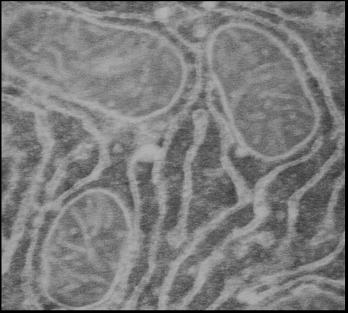

Для более точного доказательства локализации белка с м.м. 57 кДа во внутренней мембране митохондрий было проведено электронно-микроскопическое исследование срезов тканей печени и сердца с использованием АТ на белок с м.м. 55 кДа. Идентификации эндогенного белка-канала и его связывание с АТ проводились с помощью вторичных антител, меченых коллоидным золотом (диаметр гранул – 10 нм). Как видно из рисунка 21, такого рода гранулы золота локализуются во внутренней мембране митохондрий как печени (Рис.21а), так и сердца (Рис.21б), причем в сердце их больше, что соответствуют данным о большей плотности митоКАТФ каналов в митохондриях сердца. Локализуются эти каналы ближе к месту контакта внутренней и внешней мембраны митохондрий, что особенно проявляется с митохондриях сердца (Рис.21б).

Рис.21а. Электронная микроскопия среза гепатоцита крысы. а - Срезы инкубированы с антителами к митохондриальному К+-транспортирующему белку. Черные гранулы (указаны стрелкой) -сайты локализации К+-транспортирующего белка с м.м. ~ 55 кДа в митохондриях.

Рис.21 б. Митохондрии и саркоплазматический ретикулум (СР) на срезе кардиомицитов крысы. Срезы инкубированы с антителами к митохондриальному К+-транспортирующему белку. Черные гранулы- сайты локализации К+-транспортирующего белка с м.м. ~ 57 кДа в митохондриях, а также сайты связывания антител с СР.

Такие же гранулы (Рис.21А) обнаружены и в ретикулюме, особенно в месте его слияния с мембраной митохондрий, что подтверждает выявленную нами методом MS-MALDI-TOF/TOF – анализа общность в структуре изучаемого белка с микросомах кальретикулином (м.м. 55 кДа).